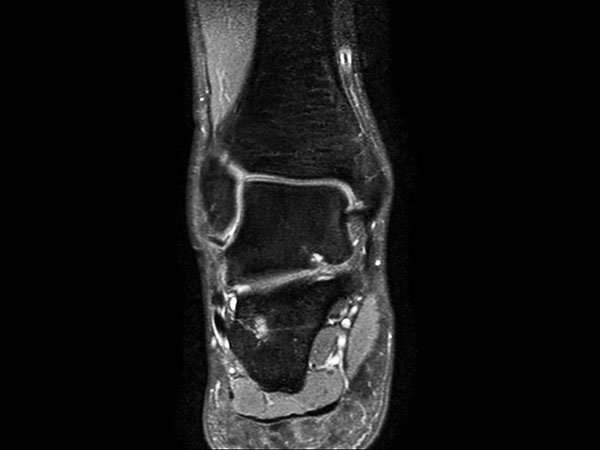

Coronal PDw mDIXON TSE  (water only)

-